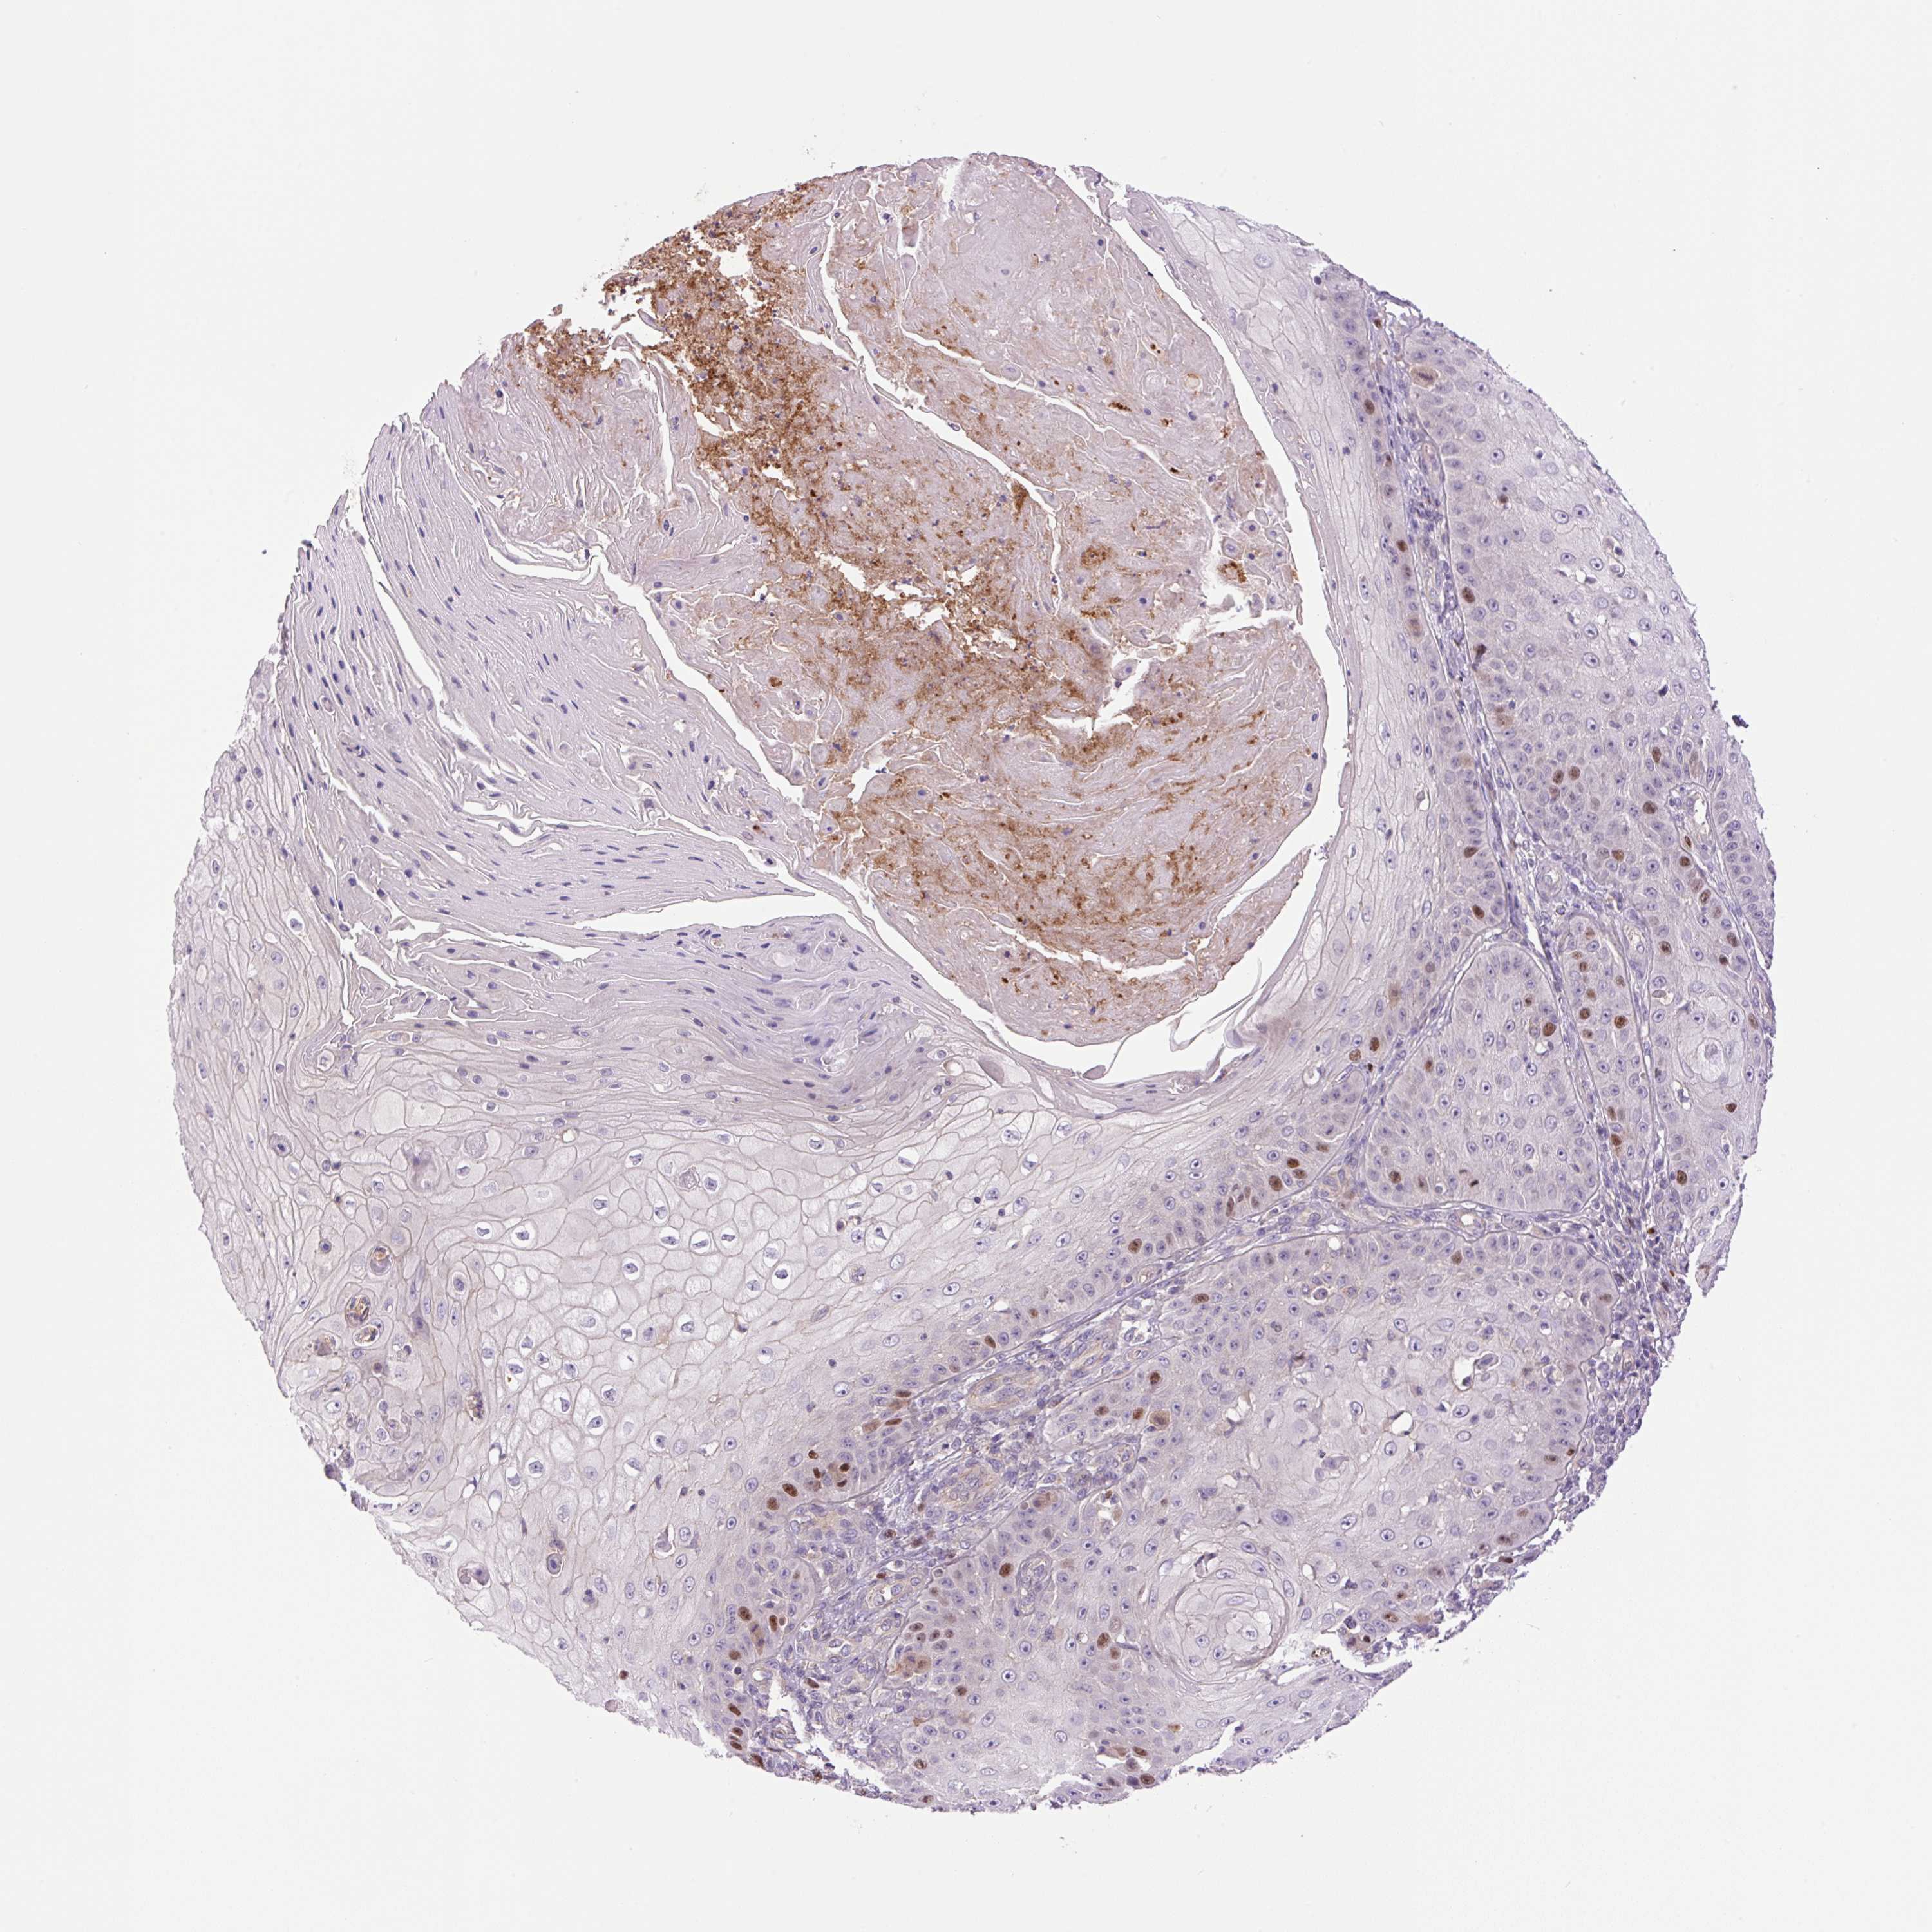

SKIN CANCER - Protein expressioni

A mouse-over function shows sample information and annotation data. Click on an image to view it in a full screen mode. Samples can be filtered based on level of antibody staining by selecting one or several of the following categories: high, medium, low and not detected. The assay and annotation is described here.

Antibody stainingi

Antibody staining in the annotated cell types in the current human tissue is reported as not detected, low, medium, or high, based on conventional immunohistochemistry profiling in selected tissues. This score is based on the combination of the staining intensity and fraction of stained cells.

Each image is clickable and will lead to virtual microscopy that enables deeper exploration of all samples and also displays staining intensity scores, fraction scores and subcellular localization as well as patient and tissue information for each sample.

Antibody HPA055997

Staining

High

Medium

Low

Not detected

Intensity

Strong

Moderate

Weak

Negative

Quantity

>75%

75%-25%

<25%

None

Location

Nuclear

Cytoplasmic/membranous

Cytoplasmic/membranous,nuclear

Basal cell carcinoma